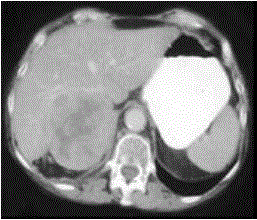

问题 女,37岁,向心性肥胖2月,请结合所提供图像,作出诊断()

选项 A.右肾上腺腺瘤 B.右肾上腺腺癌 C.右肾上腺转移瘤 D.右肾上腺嗜铬细胞瘤 E.右肾上腺增生

答案 B